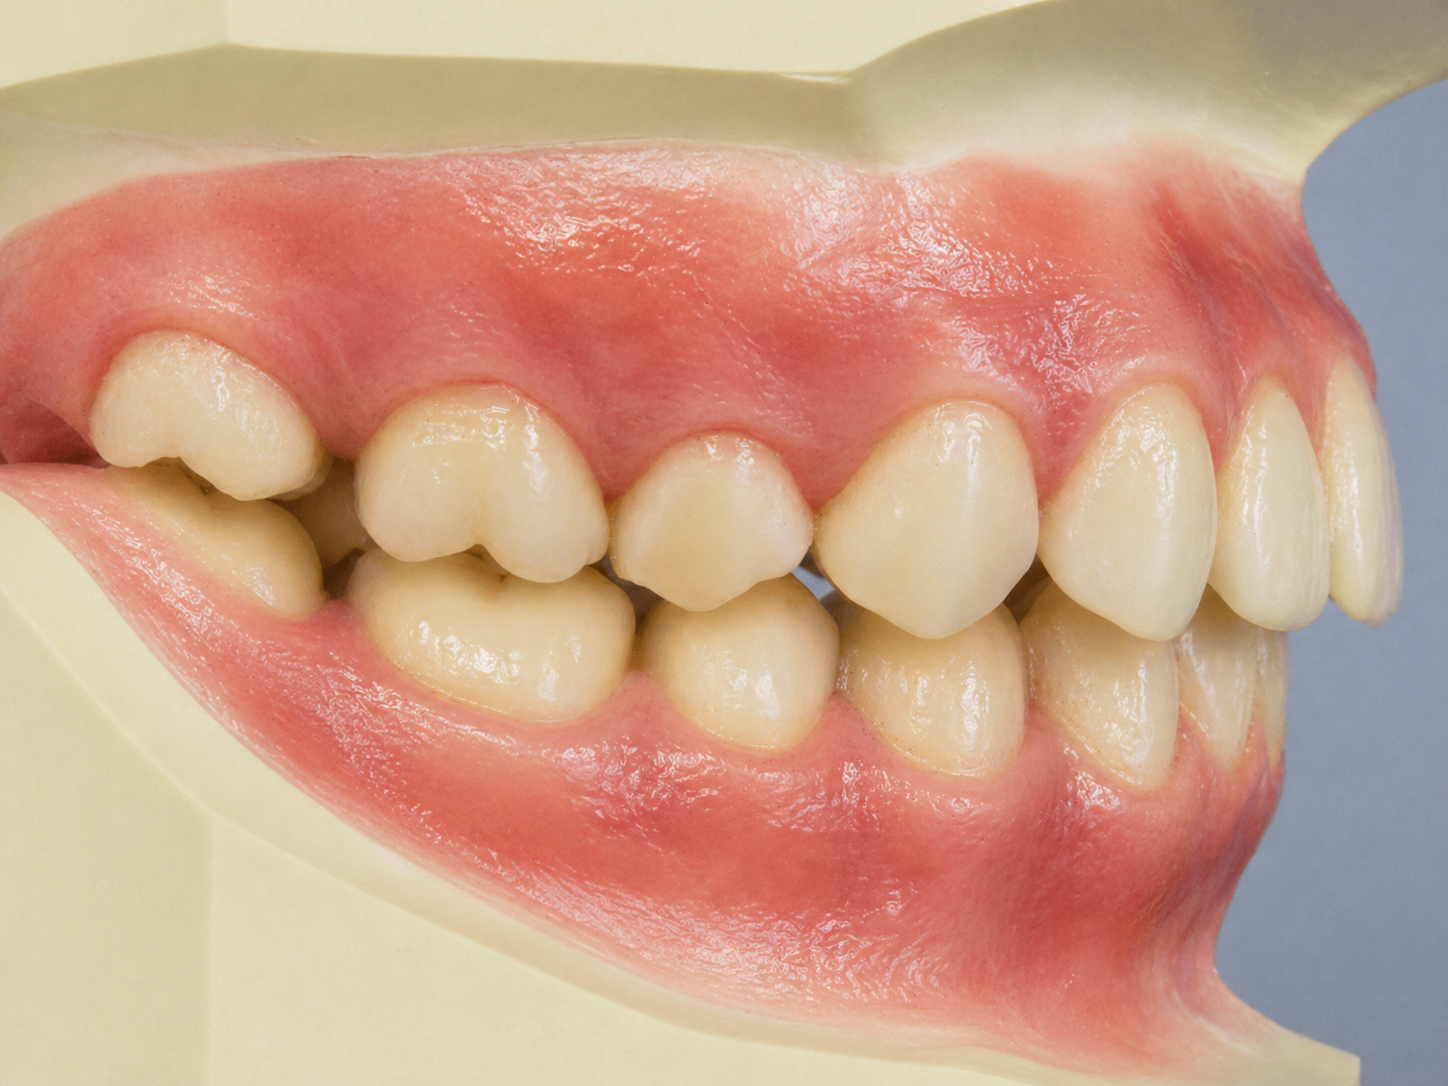

顎が後退すると、横顔が変わる

顎の骨格的な位置が後退することで、口元が前に出た印象になり、Eラインが崩れます。 歯並びを整えても、根本の顎位置が変わらなければ横顔は変わりません。

骨格から整えることが本質

SmarteeGSは顎を正しい位置に誘導する装置です。 顎の位置から変えることで、自然な横顔バランスを回復させます。